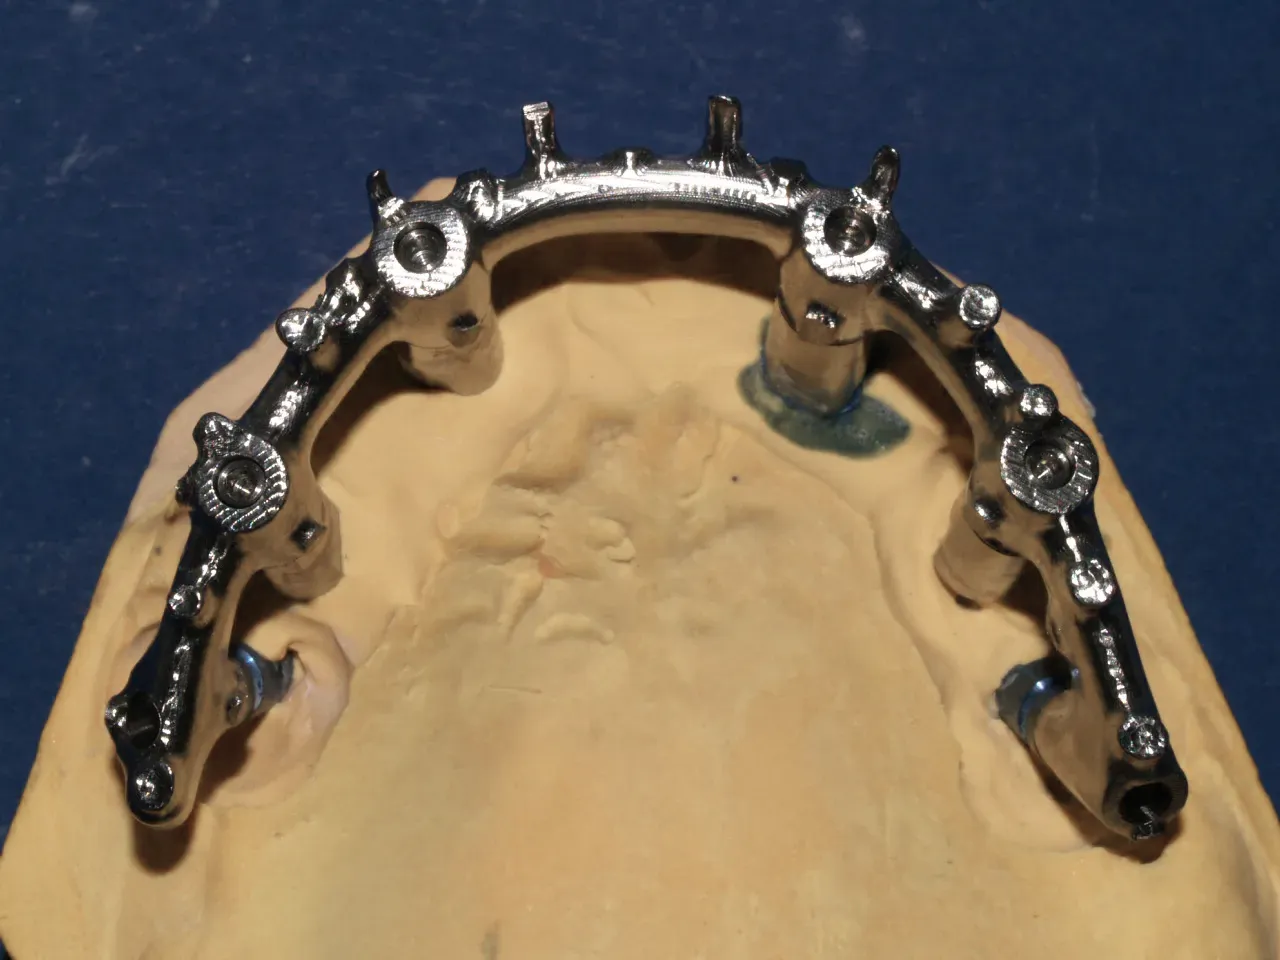

Con el paso del tiempo, ELBER evoluciona hacia un modelo técnico–digital, integrando nuevas tecnologías, flujo CAD/CAM e impresión 3D, sin perder el criterio clínico que ha definido su trabajo desde el inicio. Esta transición marca un punto clave: pasar de un enfoque artesanal a una operación estructurada, precisa y orientada al rendimiento.

Combinamos experiencia clínica con tecnología digital avanzada para lograr mayor precisión, mejor ajuste y resultados consistentes en cada caso.

Nuestro flujo CAD/CAM e impresión 3D profesional permiten optimizar tiempos, controlar procesos y garantizar restauraciones funcionales desde la primera prueba, siempre con acompañamiento técnico directo y comunicación fluida con la clínica.

Producción digital con criterio técnico

Integramos diseño CAD/CAM, impresión 3D y acabado manual especializado para optimizar cada fase del proceso. Nuestro enfoque combina tecnología avanzada con control técnico, garantizando ajustes exactos, consistencia clínica y resultados reproducibles.